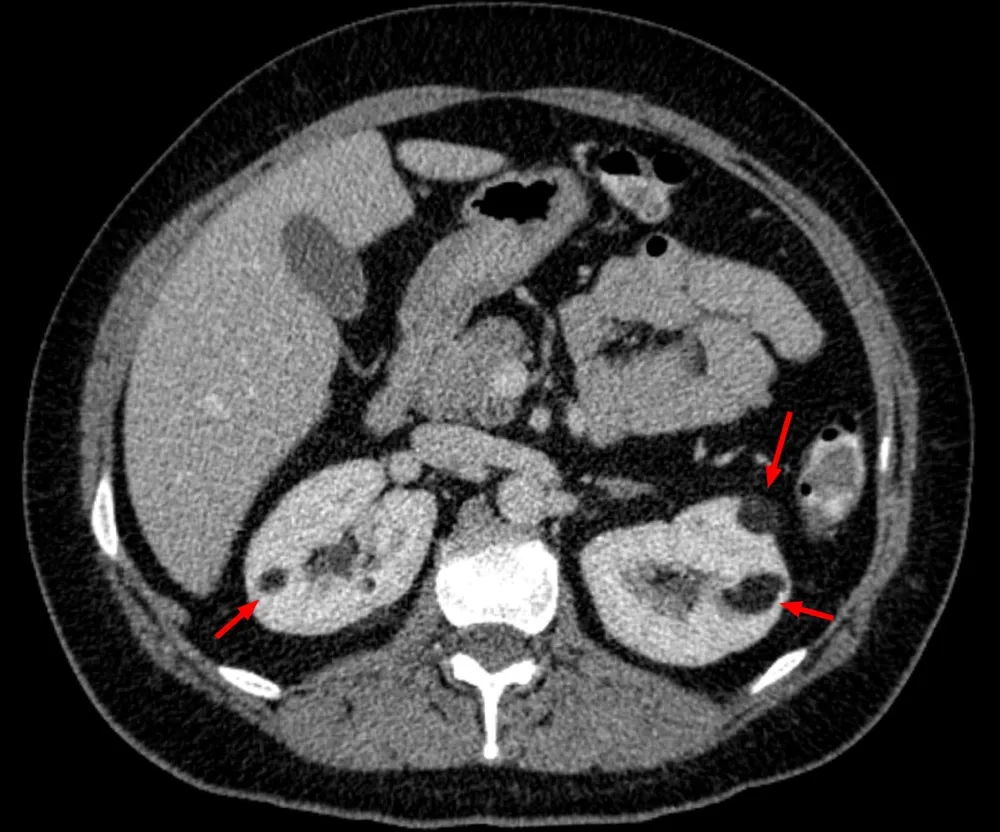

IRA + Icterícia: Um Caso que Exige Investigação Detalhada

IRA + Icterícia: Um Caso que Exige Investigação Detalhada